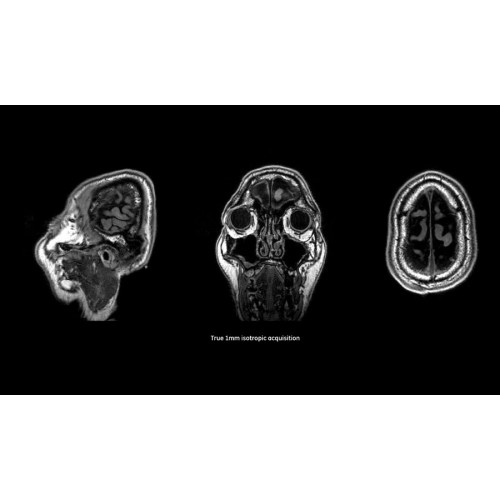

Система SIGNA Pioneer воплощает поразительные достижения в области визуализации. Передовая технология Total Digital Imaging (TDI) позволяет добиться большей четкости изображений и на четверть повысить соотношение сигнал/шум.

• Технология Direct Digital Interface (DDI) использует независимый аналого-цифровой преобразователь для оцифровки сигнала от каждого из 97 радиочастотных каналов, что обеспечивает значительное увеличение качества за счет уменьшения фонового шума.

• Технология Digital Surround Technology (DST) — это новая технология объемной оцифровки данных, объединяющая сигналы от каждого элемента катушки. Прекрасное соотношение сигнал/шум и чувствительность поверхностных катушек в сочетании с превосходной однородностью и высокой проникающей способностью встроенной радиочастотной катушки — все это позволяет создавать качественные изображения не только позвоночника, но и всего тела.